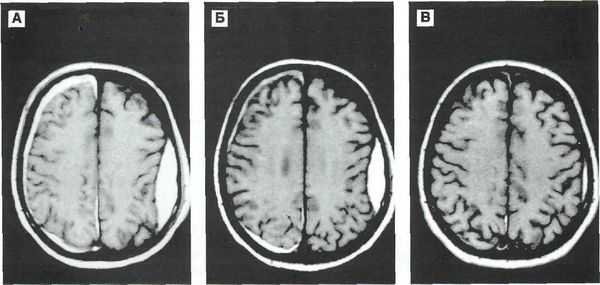

- КТ головного мозга. Как правило, на томограммах внутримозговая гематома имеет вид очага гомогенной плотности округлой или овальной формы. Если гематома сформировалась в результате ушиба головного мозга, то она обычно имеет неровный контур. С течением времени происходит уменьшение плотности гематомы до изоплотного состояния, при котором ее плотность соответствует плотности мозговой ткани. Для малых гематом этот период составляет 2-3 недели, а для средних — до 5 недель.

- МРТ головного мозга. При уменьшении плотности гематома лучше визуализируется при помощи МРТ, хотя в начальном периоде применение МРТ может привести к ошибочному диагнозу в пользу опухоли с кровоизлиянием. Поэтому, при наличие такой возможности, многие неврологи и нейрохирурги предпочитают использовать в ходе диагностики оба способа нейровизуализации (КТ и МРТ).